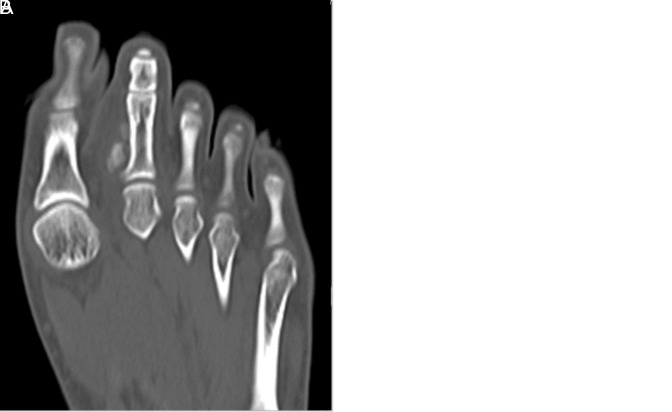

Florid Reactive Periostitis of the Toe.

脚趾弗洛里反应性骨膜炎